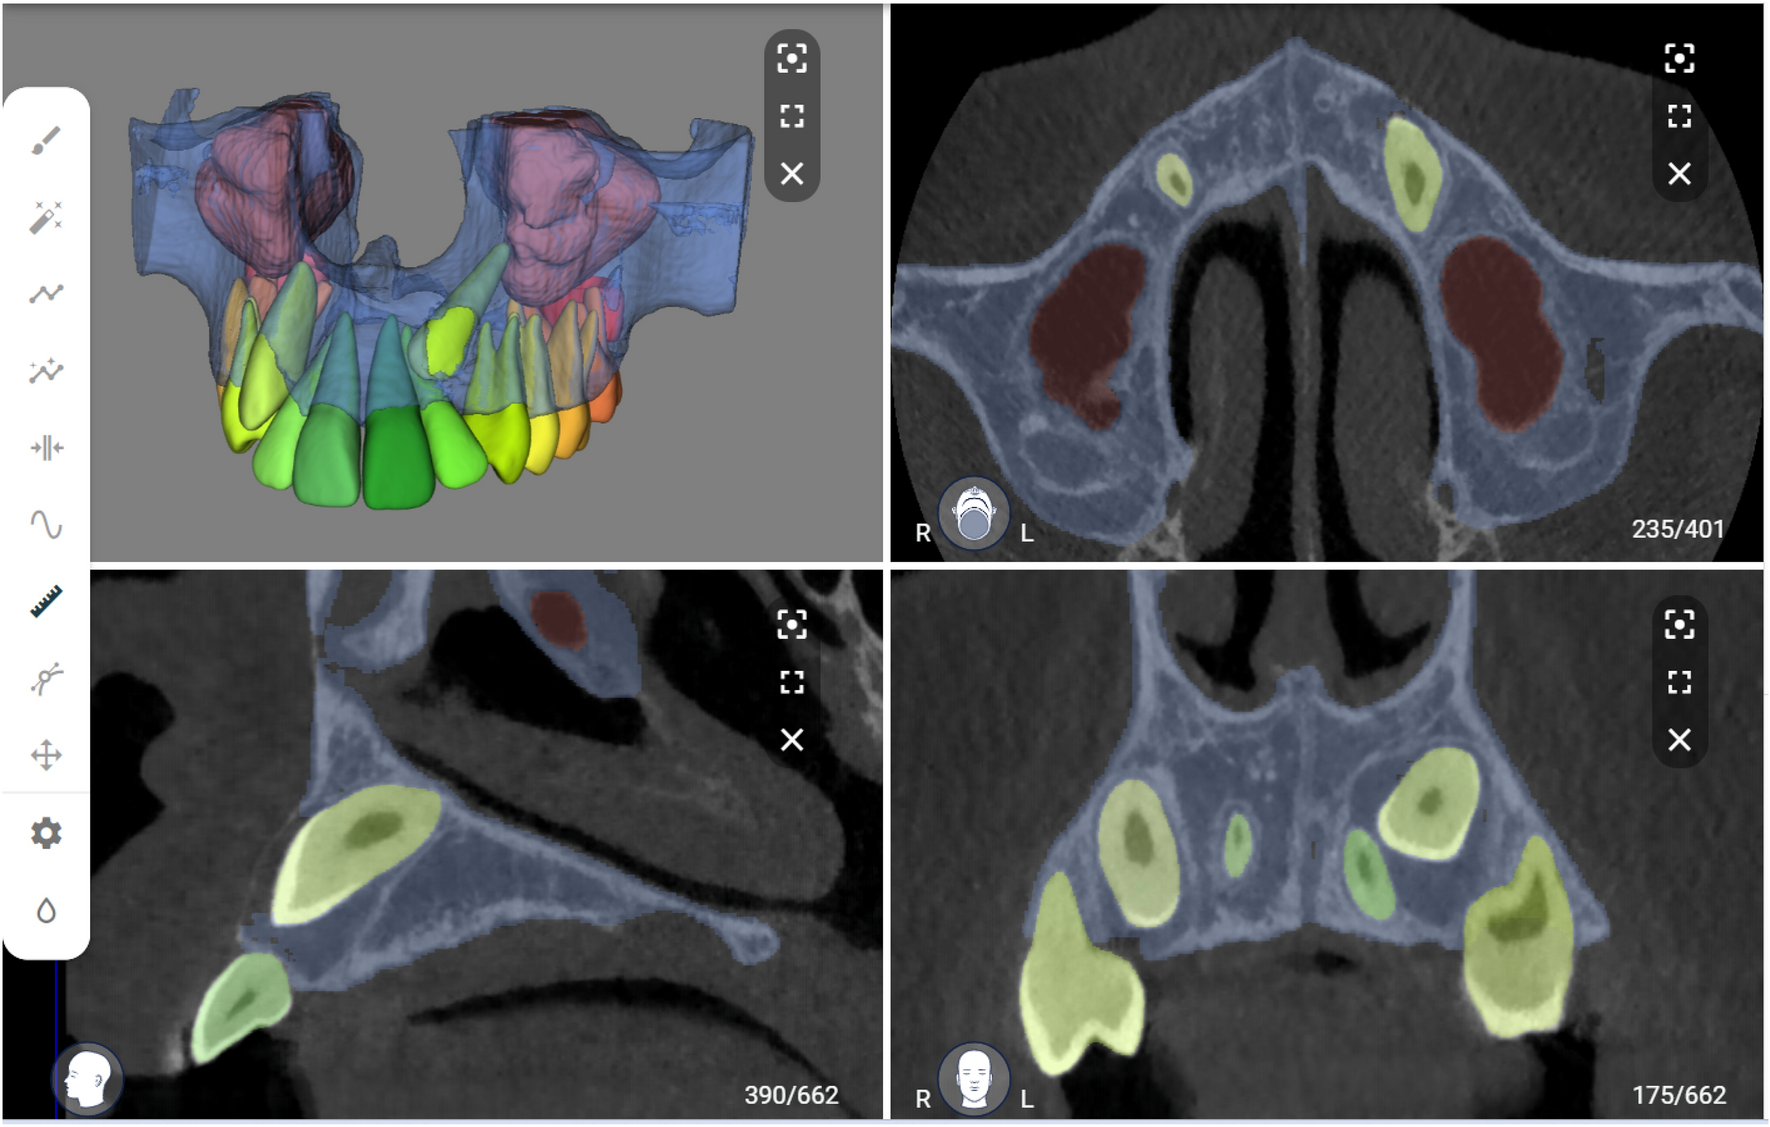

Figure 3

Automated segmentation of maxillary impacted canine and other dentomaxillofacial structures (maxillary bone, maxillary sinus and erupted teeth) on virtual patient creator platform (creator.relu.eu, Relu BV, Version October 2022).